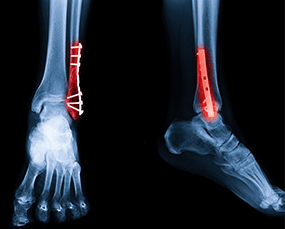

Dr. Ankur Singh offers advanced orthopedic services focused on precise treatment, fast recovery and personalised patient care for effective bone and joint health.

Advanced Ortho & Trauma Solutions

From consultation to post-operative care, our clinic in Noida ensures accurate treatment plans and superior outcomes in orthopedic and trauma care.